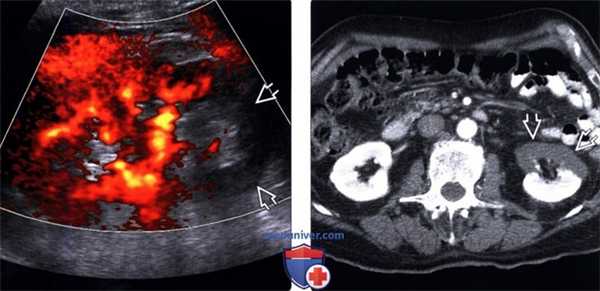

(Левый) У пациента с дилатационной кардиомиопатией в нижнем полюсе правой почки при УЗИ визуализируется слабо выраженный клиновидный гиперэхо генный инфаркт. На соответствующем КТ срезе с контрастированием визуализируется дефект контрастирования в этой области. Обратите внимание на неизмененное контрастирование капсулы (симптом «кортикального края»), обусловленное интактностью капсулярных артерий, кровоснабжающих капсулу.

(Правый) При цветовой допплерографии в верхнем полюсе почки у пациента с сегментарным инфарктом почки кровоток не визуализируется.

(Левый) При цветовой допплерографии визуализация кровотока в нижнем полюсе почки у пациента с инфарктом почки на фоне фибрилляции предсердий отсутствует. Наиболее чувствительным методом выявления медленных токов является энергетическая допплерография, которая должна использоваться для подтверждения диагноза инфаркта.

(Правый) При КТ с контрастированием у того же пациента визуализируется отсутствие перфузии в переднем отделе коркового вещества почки.